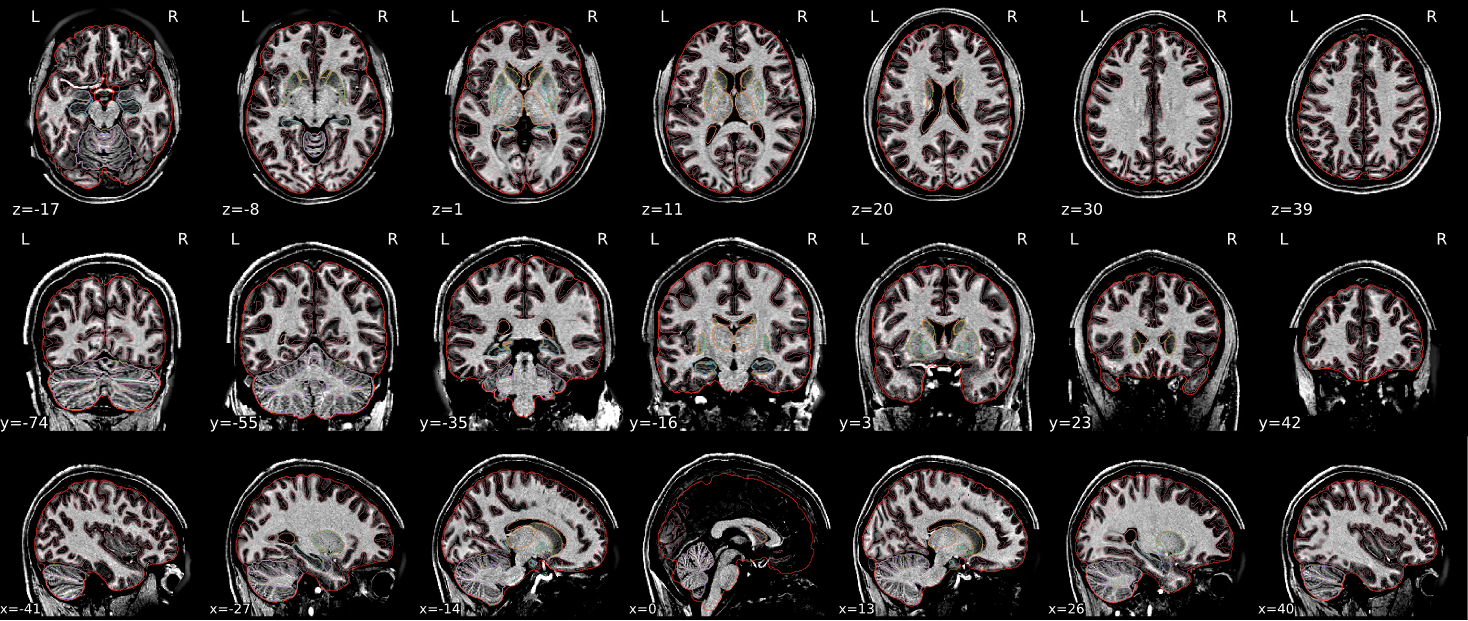

EPI spatial normalisation

This QC step shows the registration of the EPI image to MNI space.

Example of a good subject

- If the registration performed well, you should see an overlap (i.e., correspondence of structures) between the MNI template and the EPI registered to the MNI space.

- If parts of the brain are missing due to the scanner field of view, this is fine. For example, the cerebellum may be cut off for a participant with a large head.

Example of a bad subject

- In case of poor registration, you should see a misalignment of the EPI and the MNI template

Summary

| good | bad |

|---|---|

| Overlap (i.e. match of structures) between the MNI template and the EPI registered in the MNI space | Misalignment of the EPI and the MNI template |

| If parts of the brain are missing because the field of view of the scanner is limited, the EPI spatial normalisation does not have to be excluded e.g. cerebellum cut off in person with large head |

If parts of the brain are missing because the field of view of the scanner is limited, the EPI spatial normalisation does not have to be excluded (e.g. cerebellum cut off in person with large head)